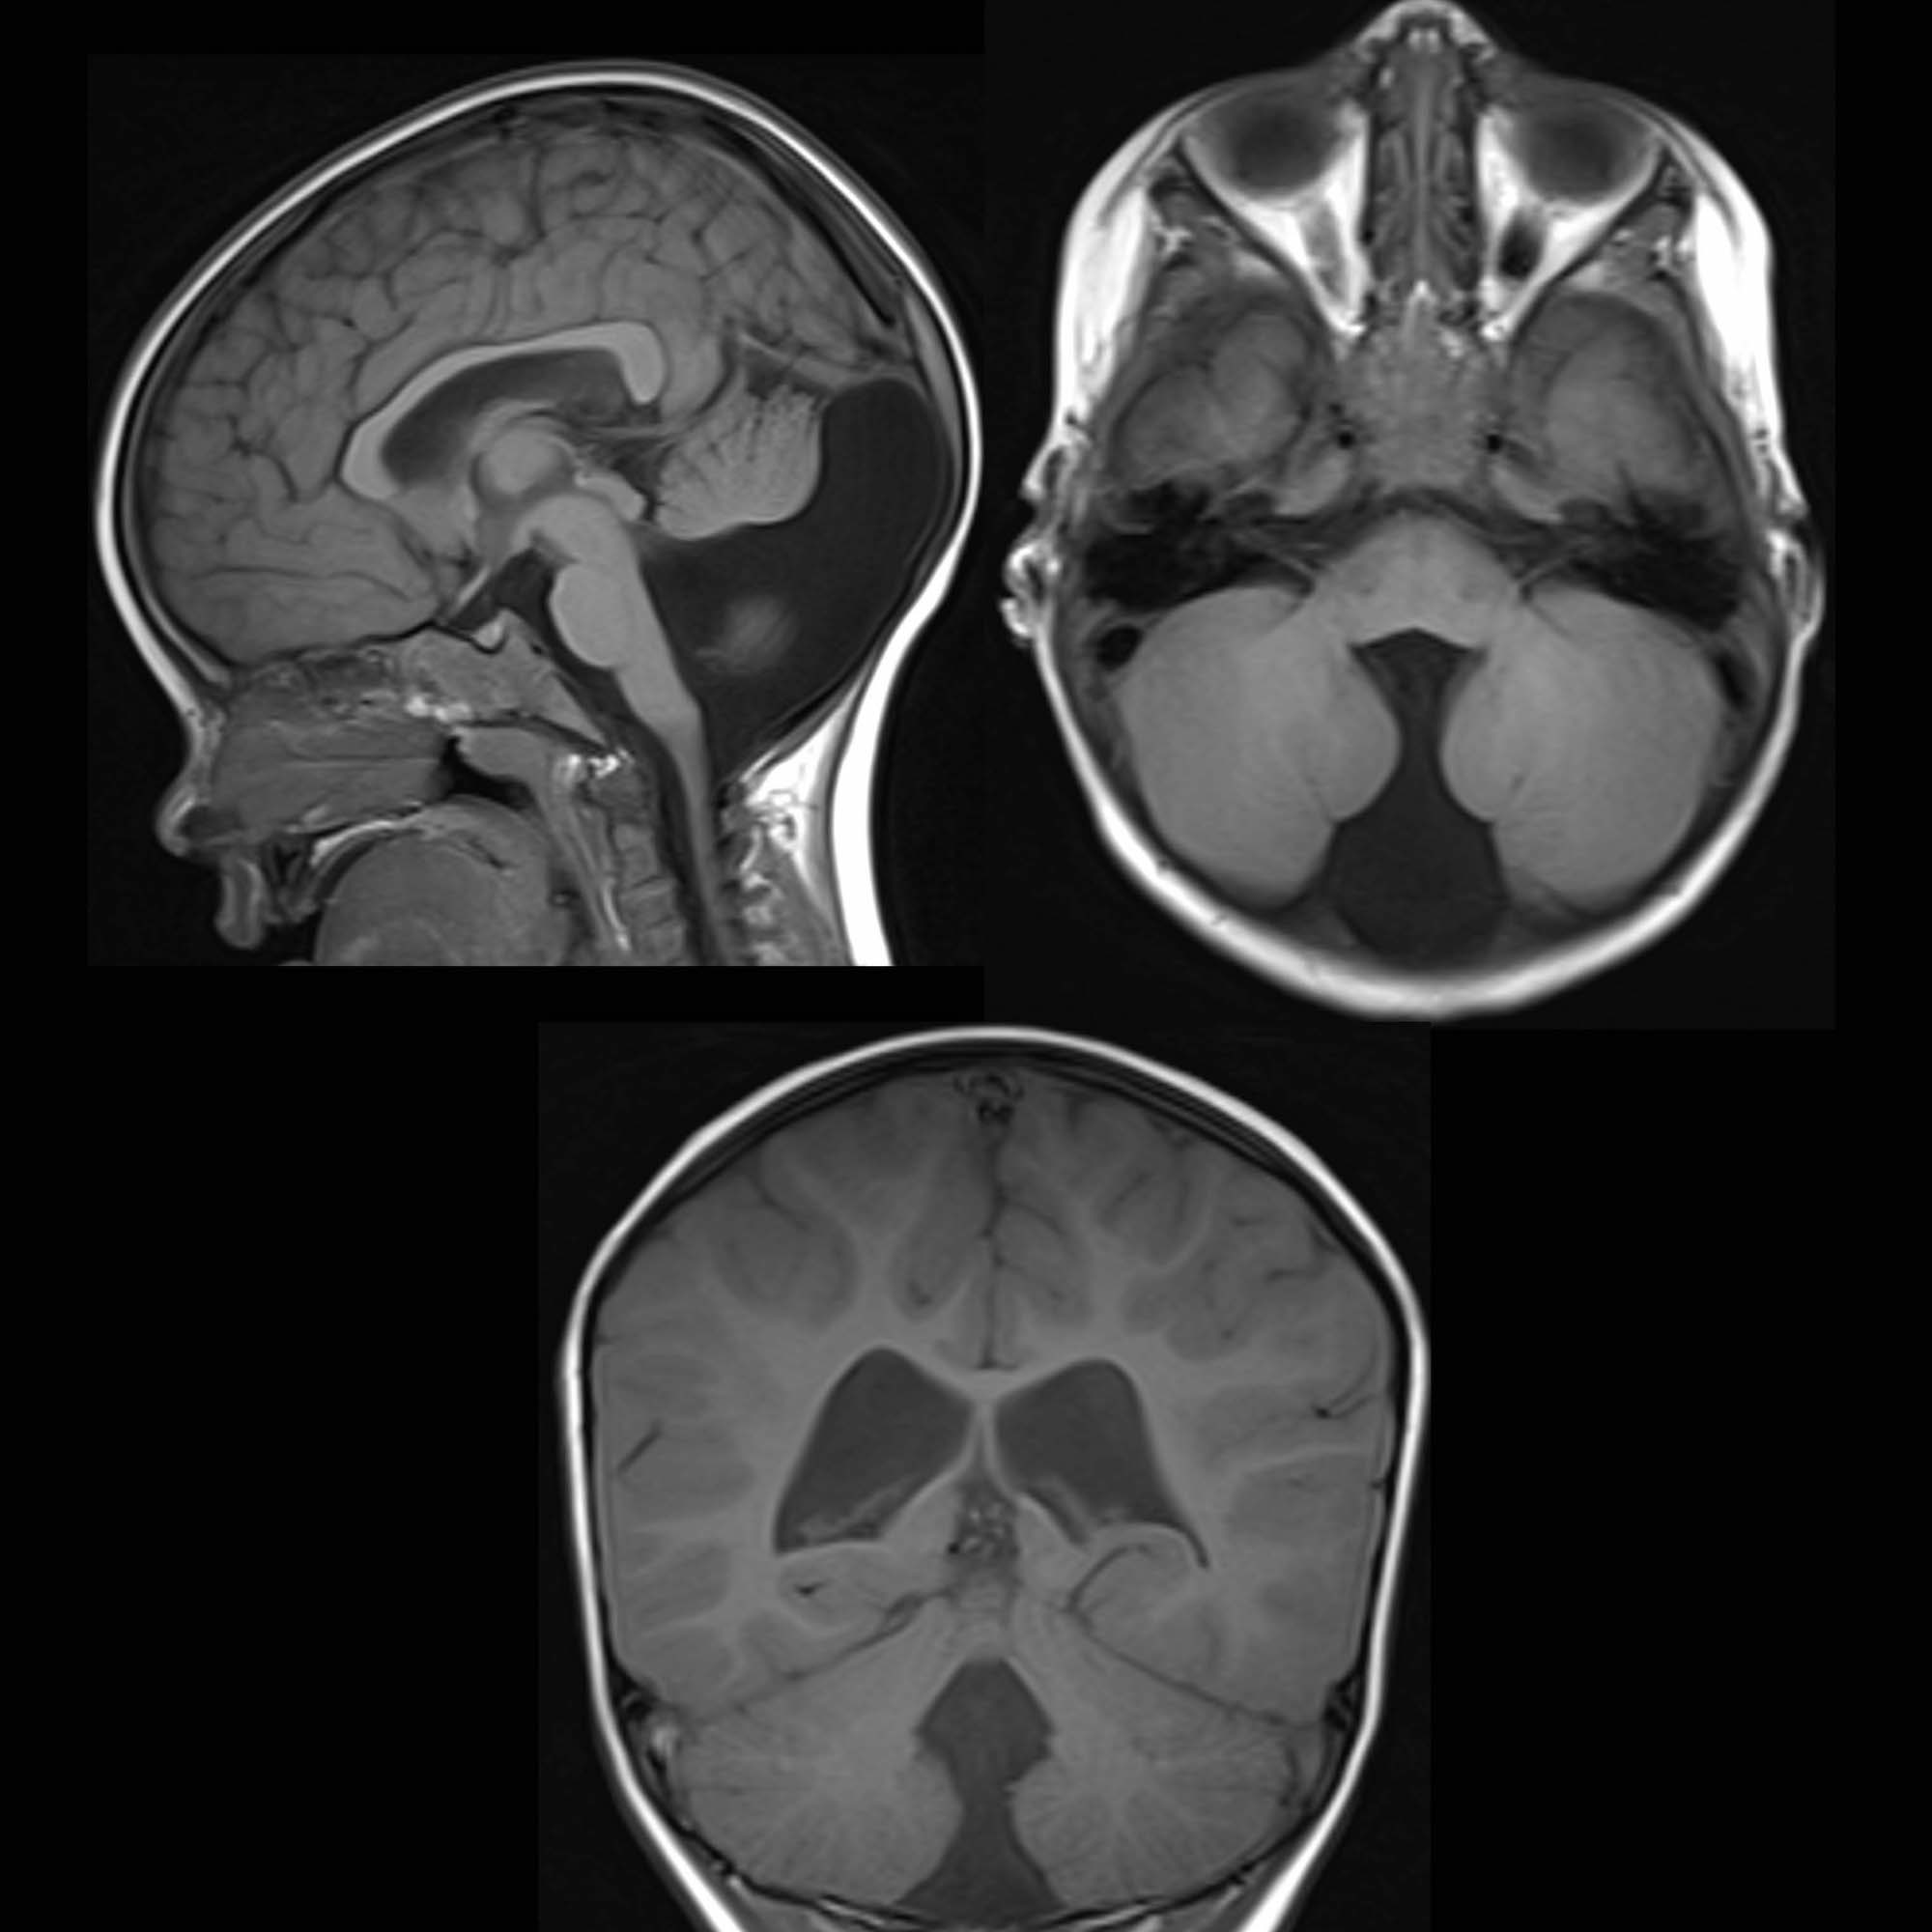

Dandy Walker malformation

agenesis/hypoplasia of cerebellar vermis resulting in cystic enlargement of 4th ventricle

can exist with or without hydrocephalus

can be hypotonic & ataxic